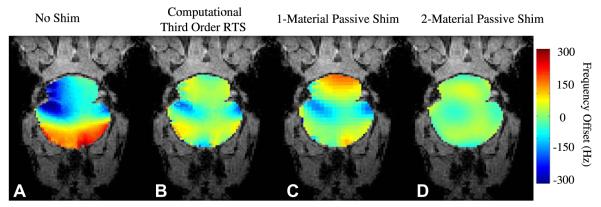

Fig. 8 shows the effects of increasing orders of shim inclusion in the whole-brain least-squares optimization of B0 field homogeneity in the human brain at 3T. It is clear from the field-maps that low-order RT shimming leaves significant residual inhomogeneity. While there is a clear advantage of going from first (B) to second (C) order shimming, with the use of third-order shimming (D), there is significantly less improvement in homogeneity compared to second-order shimming (C).

Fig. 8.

(A) Axial MRI at B0 = 3T of two axial slices encompassing the sinus cavity region, residual inhomogeneity after (B) first order shimming, (C) with the inclusion of second-order shims, (D) with the inclusion of third-order shims.